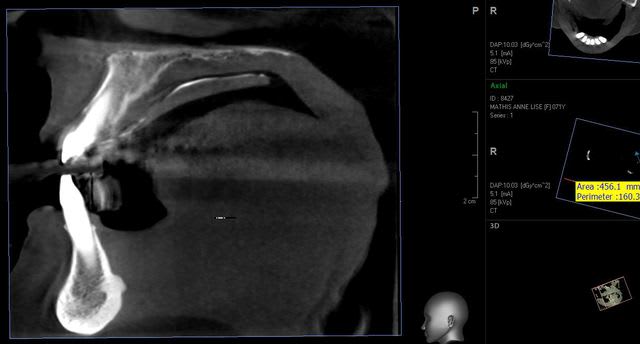

voila pour vatech,

le logiciel est beaucoup plus facile d'utilisation mais la précision laisse tout de même à désirer

Capture vatech s6ple1 - Eugenol

Capture vatech1 rivm62 - Eugenol

Capture vatech2 njn6uu - Eugenol